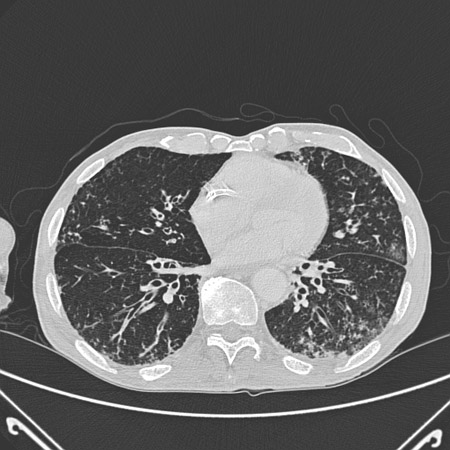

Chest CT of a patient with amiodarone pulmonary toxicity, showing asymmetric opacities with a peripheral distribution

From the personal collection of Dr A. Pataka and Professor P. Argyropoulou, Aristotle University, Thessaloniki, Greece